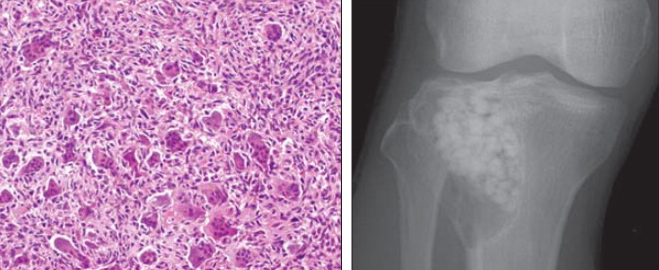

A 30 year old male presents with knee pain. His radiograph and biopsy are shown below. What is your diagnosis? Prognosis?

Benign giant cell tumor. These often occur in the epiphyseal regions of long bones and have a soap bubble appearance on x-ray. They also demonstrate spindle-shaped cells with multinucleate giant cells on a biopsy.